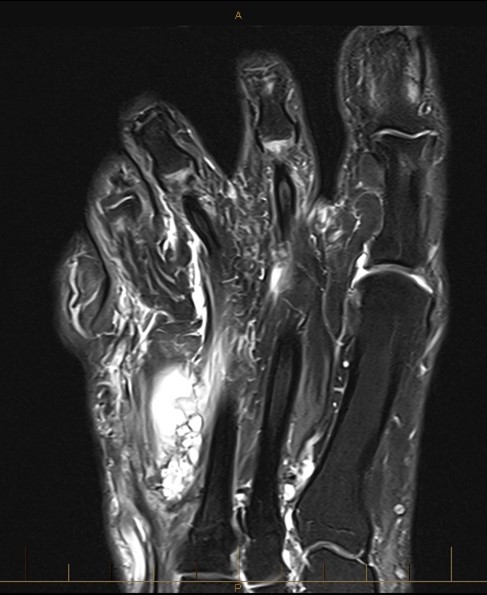

44 year old lady with a slowly growing swelling on her foot. MRI shows a multiloculated ganglion.